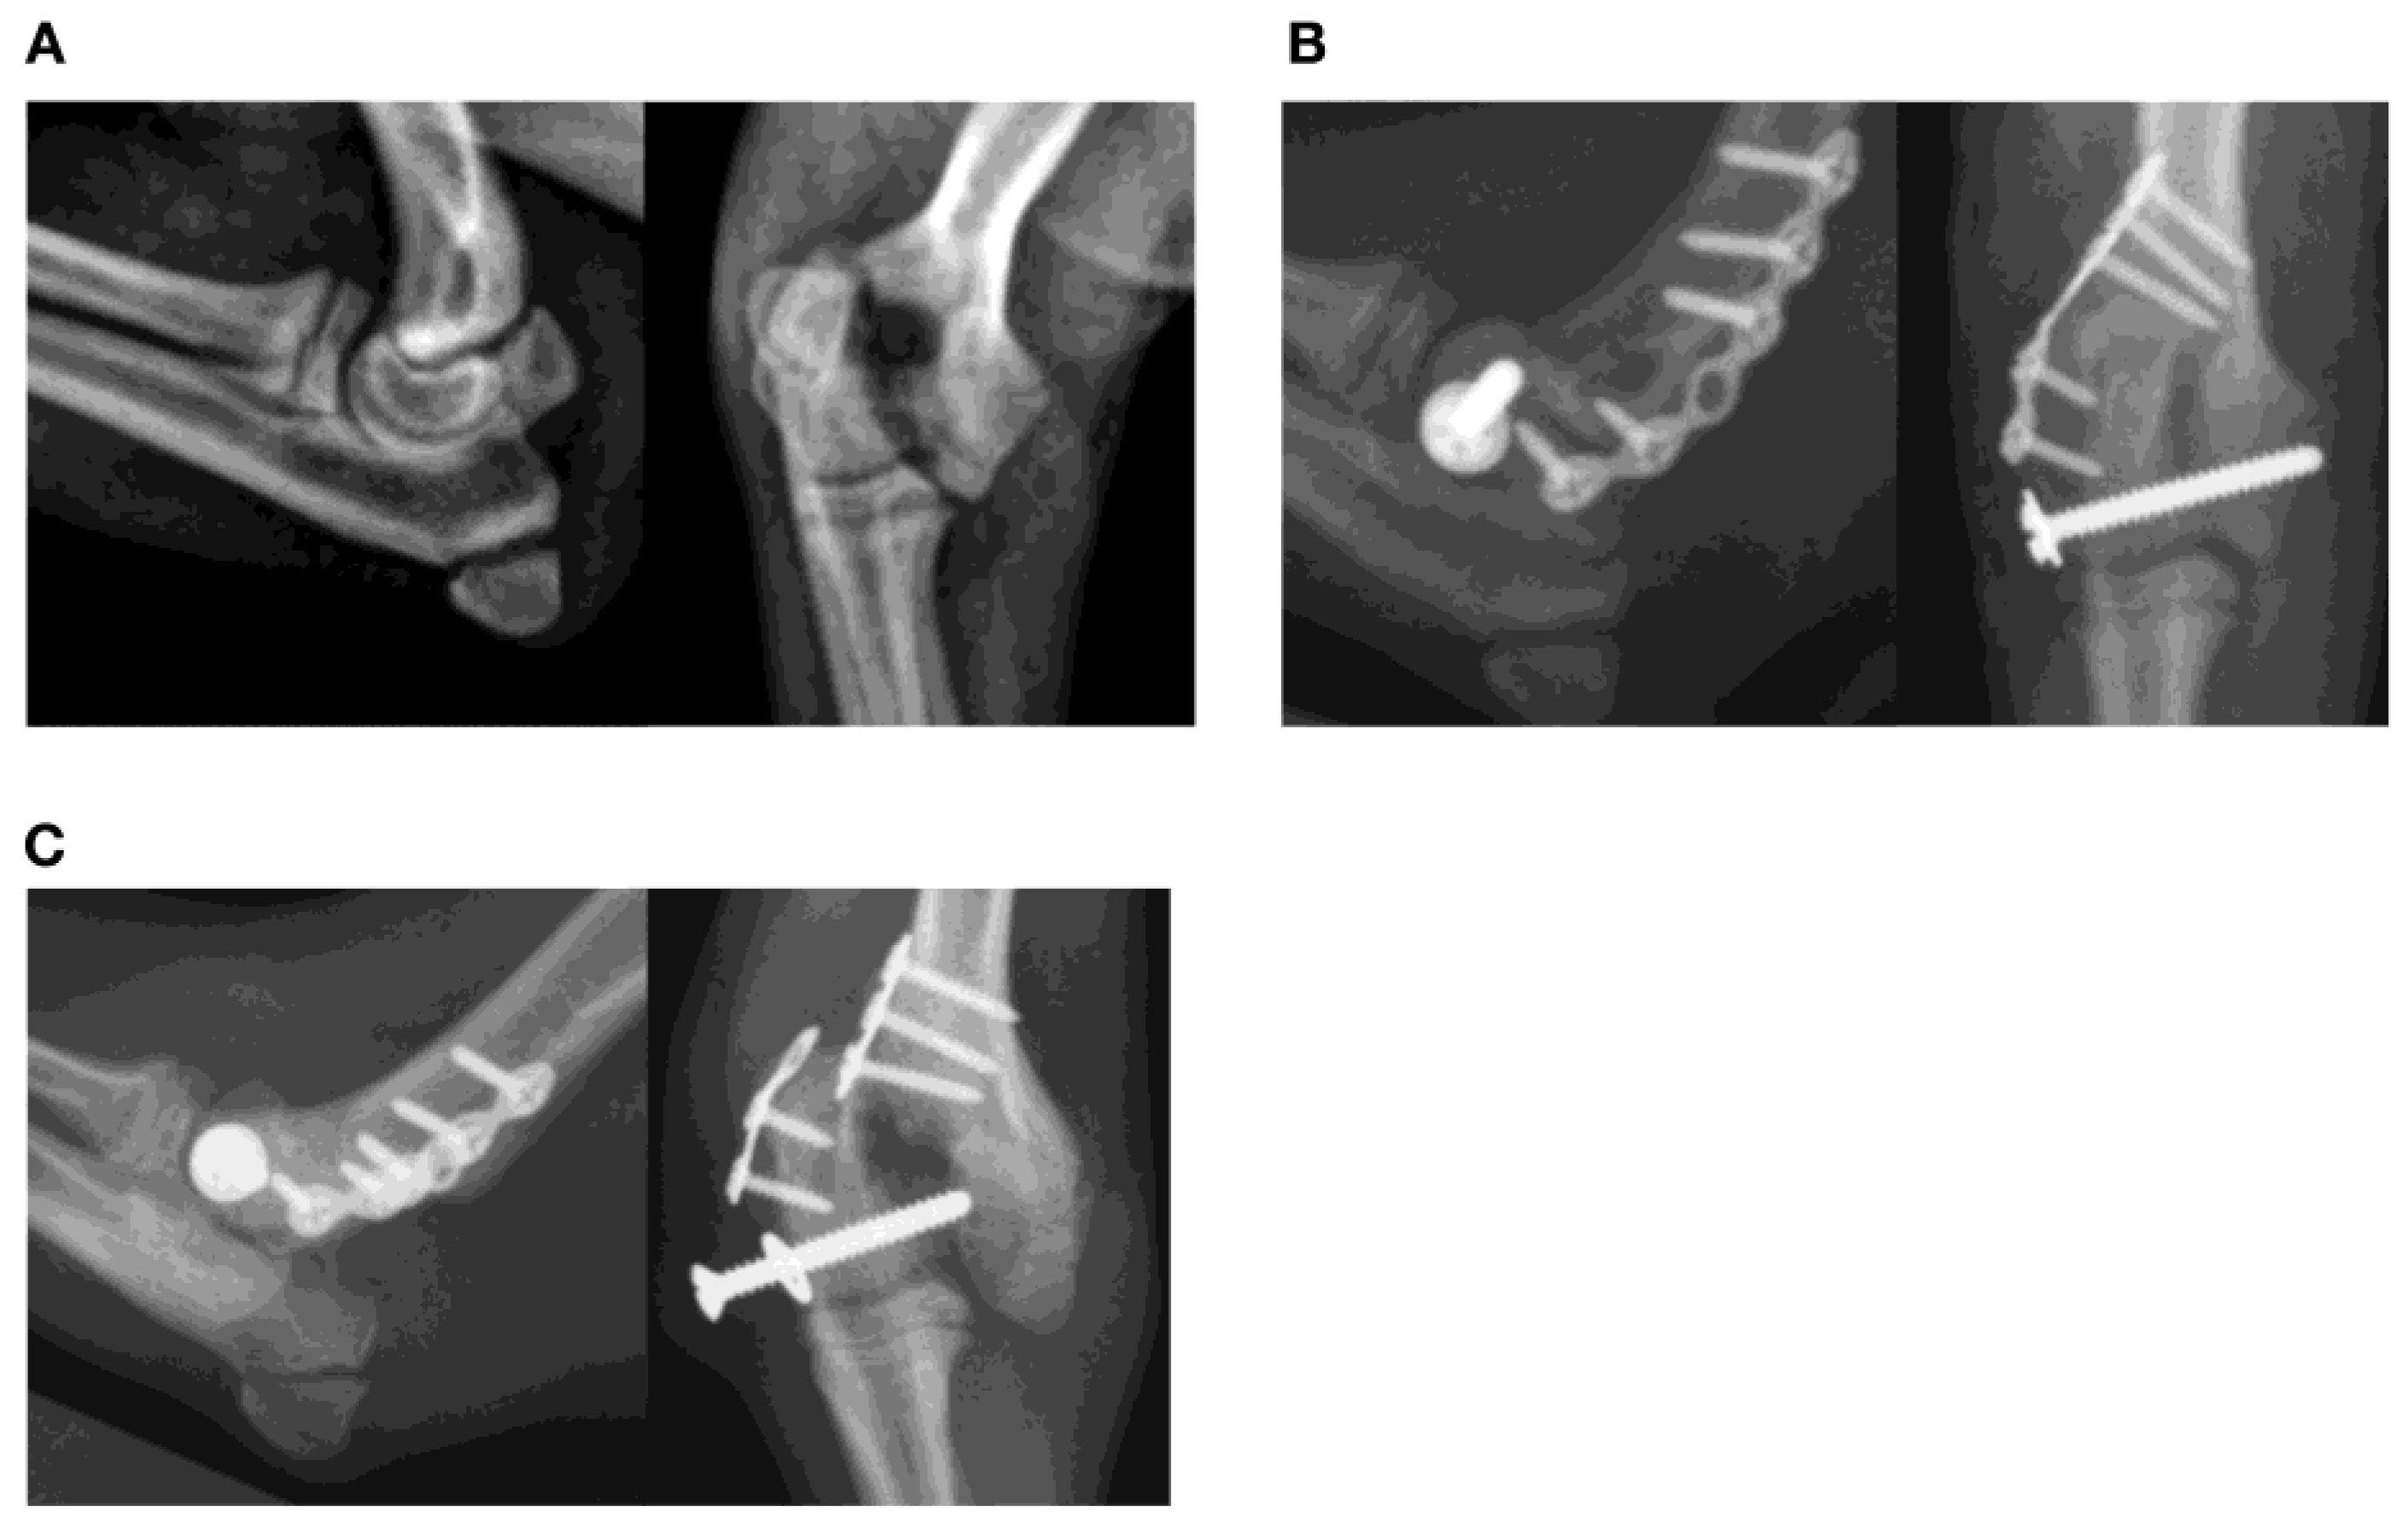

3.4. Screw Breakage (Five Fractures)

3.5. Pin/Wire Breakage or Bending (Two Fractures)